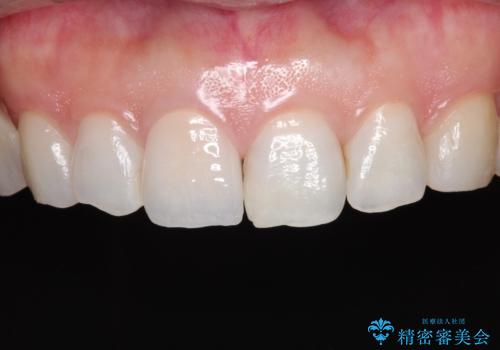

- 奥歯の被せ物が欠けたを主訴に来院された患者様です。欠けてしまった被せ物を除去後セラミックインレーで治療を行いました。

欠けた範囲が大きく被せ物を外して後、セラミックインレーで治療を行いました。欠けたままの状態を放置しているとそこに食べ物が詰まり虫歯になってしまうので早めの治療が必要です。